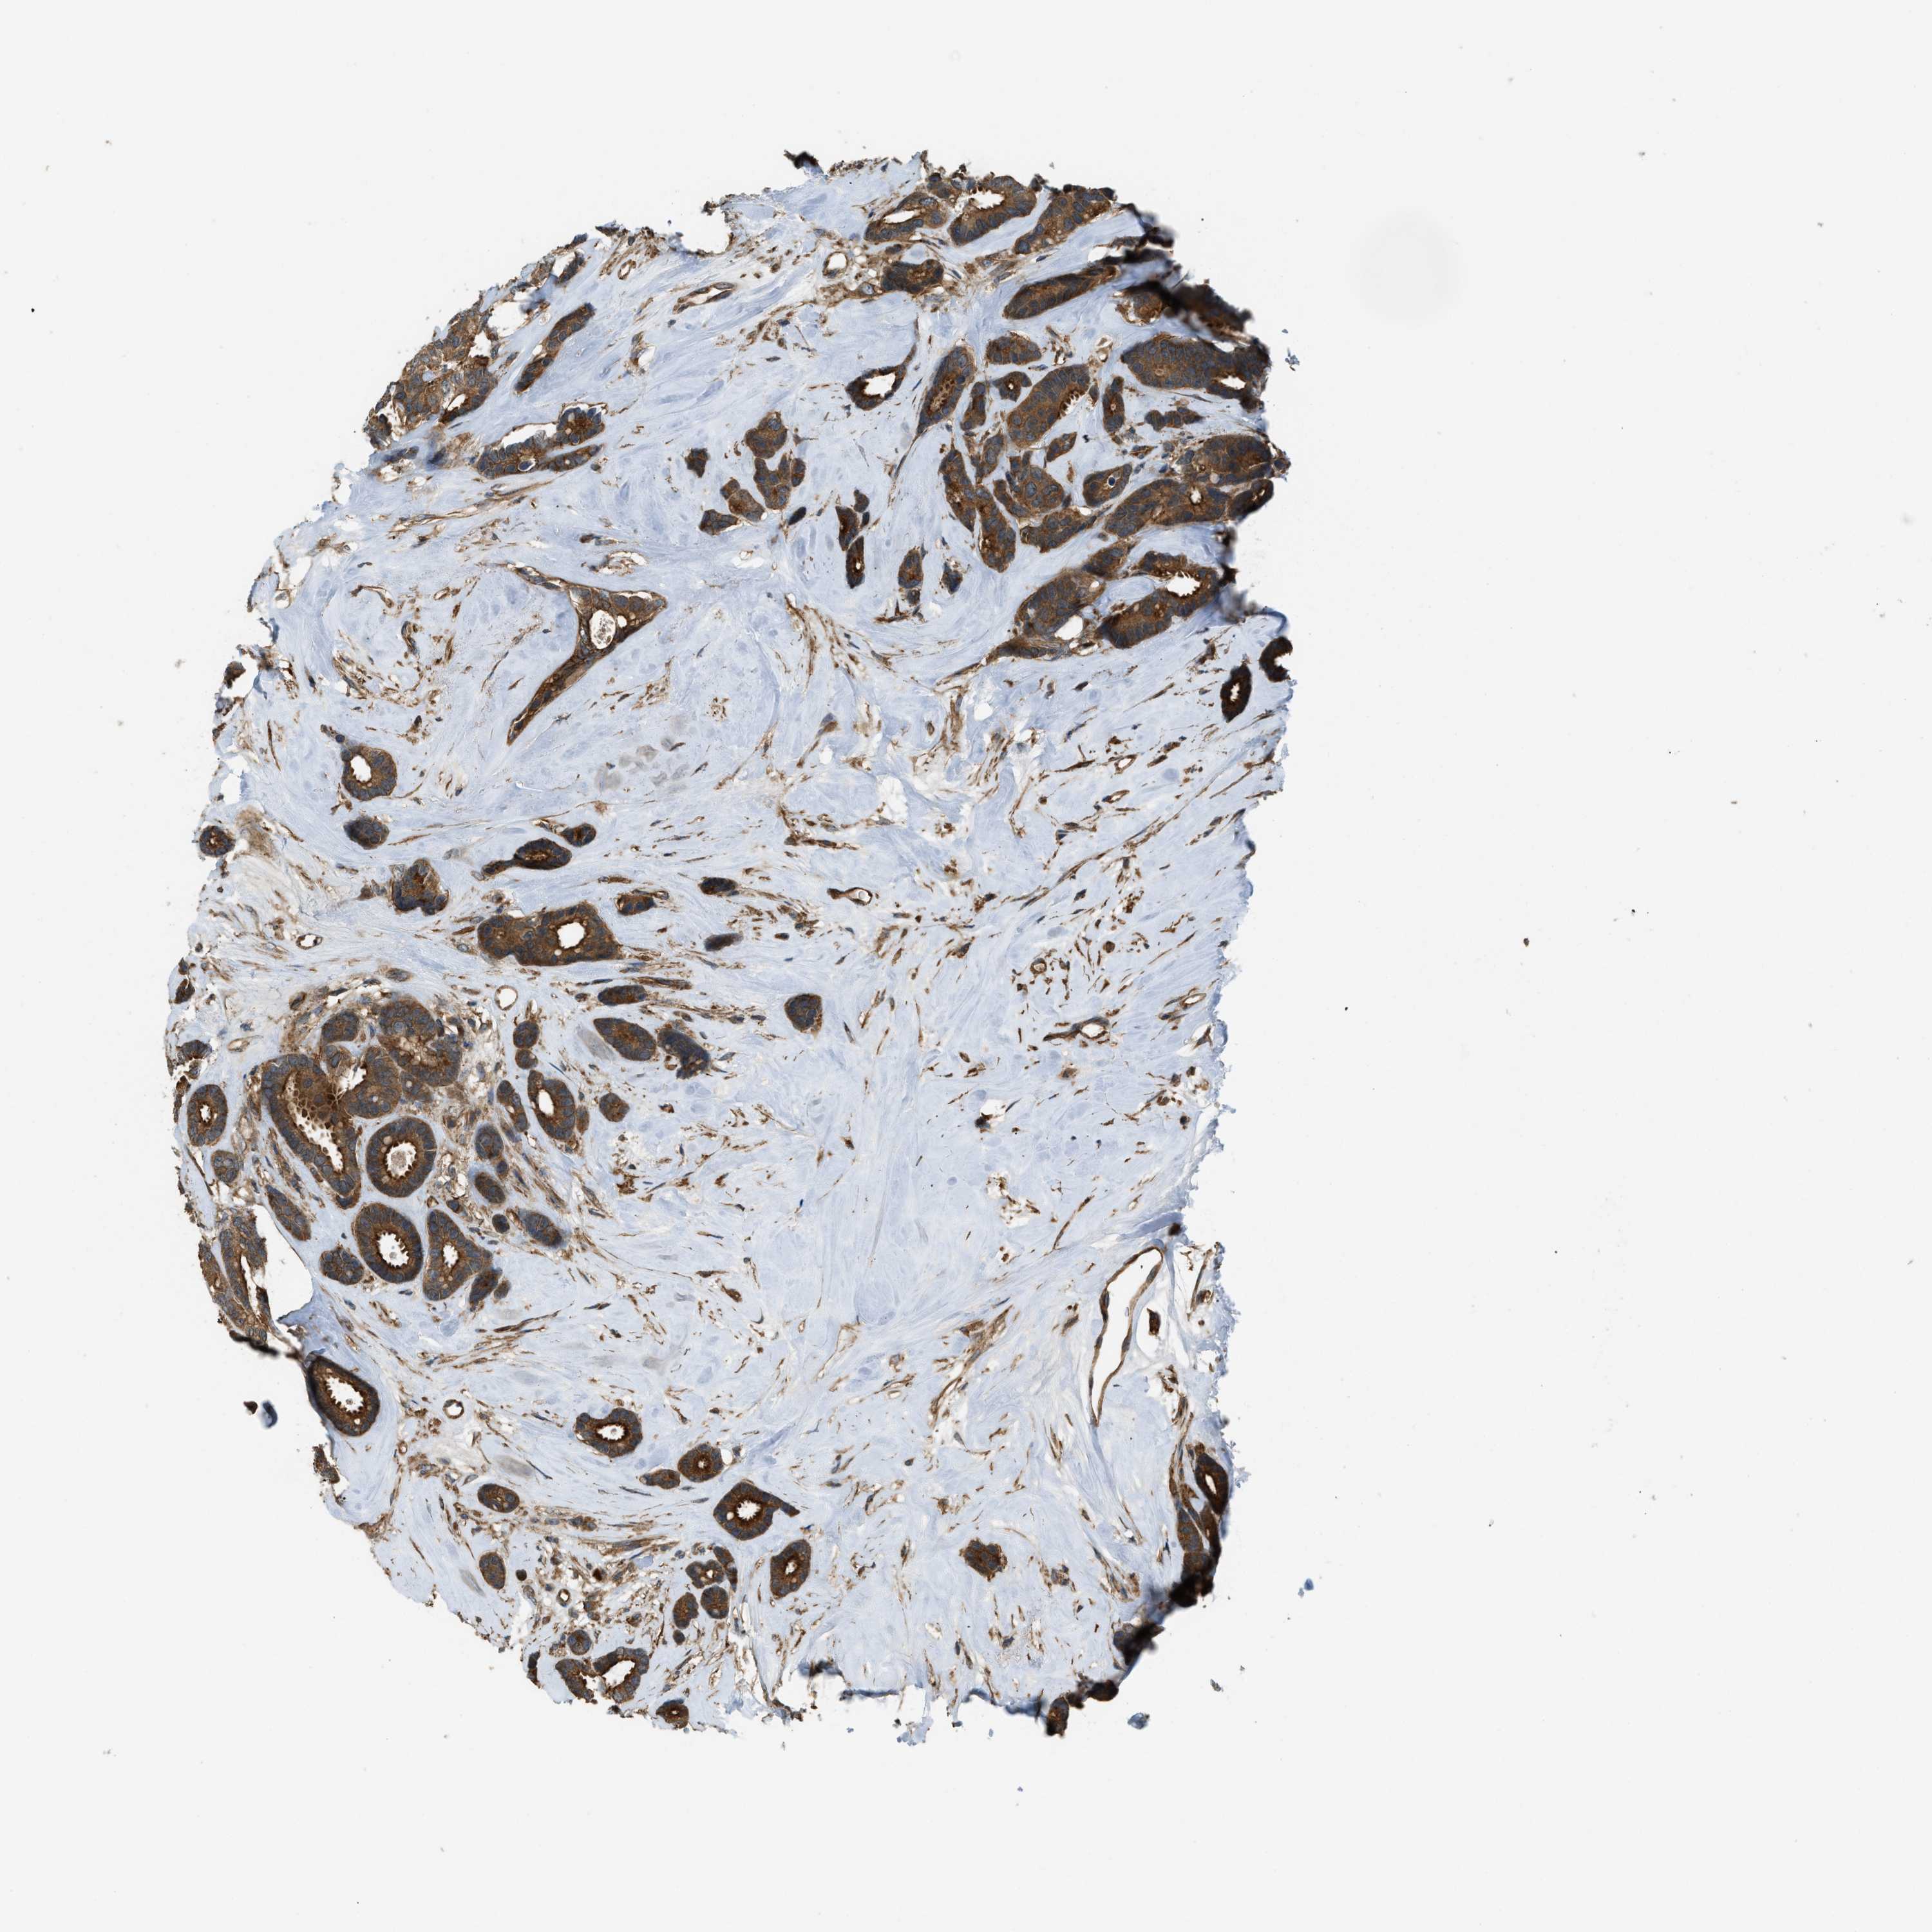

CANCER BREAST CANCER Show tissue menu

BRCA TCGA BRCA VALIDATION PROTEIN EXPRESSION

ANTIBODIES

AND

VALIDATION